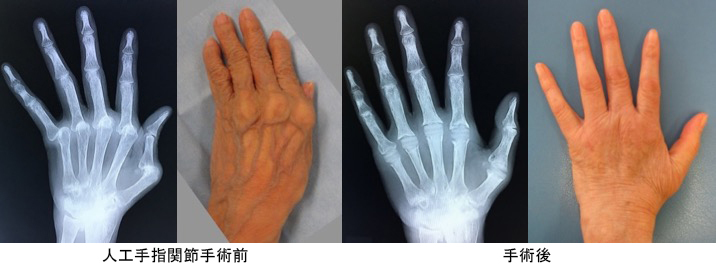

関節リウマチ

リウマチによる手・肘の変形に対する治療は一般的に難易度が高く、また習熟している施設は限られています。当院ではリウマチ手指や肘に対する人工関節手術を積極的に行い、良好な治療成績を得ています。また比較的若年の方で関節面が保たれている場合は可能な限り関節温存手術を行います。当院の担当医はリウマチ指の人工関節手術、人工肘関節手術、人工関節を用いない手指軟部組織形成術や肘関節形成術の経験も豊富です。